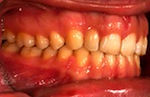

vorher

nachher

Patientin – 29 Jahre, Angle Kl. I, Invisalign für 9,5 Monate

Persistierender 52

(hier bereits entfernt)

12 war distal von 52 durchgebrochen